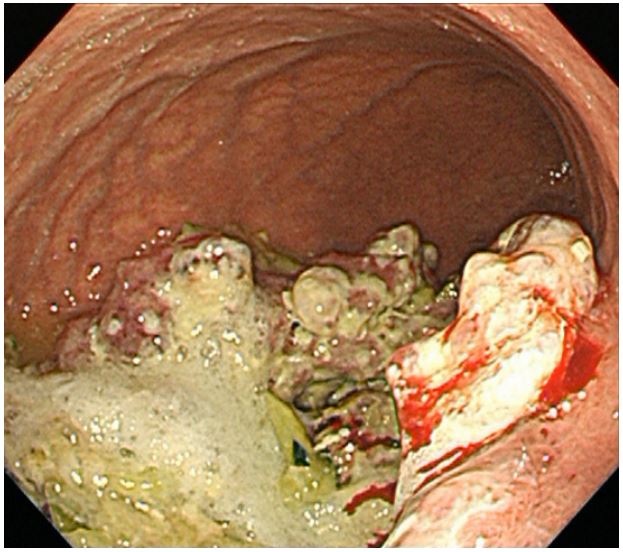

An eighty-year-old woman presented with the symptoms of abdominal pain, slight fever of 37-38°C, and body weight loss. Upper Gastrointestinal (GI) examination performed one month prior to presentation revealed a gastric tumor, while Esophagogastroduodenoscopy (EGD) showed a type 3 tumor in the gastric fundus and corpus (Figure 1a). However, food residues covering the tumor surface prevented precise observation. Colonoscopy revealed an irregular surface elevation in the splenic flexure of the colon (Figure 1b), in which an adenocarcinoma was detected by biopsy. Contrast-enhanced computed tomography (eCT) revealed advanced GC with extensive invasion of the transverse colon, spleen, and pancreas (Figure 2a,b). Peritoneal dissemination and lymph node metastasis were suspected. The eCT image also showed gas in the pancreatic duct, indicating fistulation from the stomach to the pancreatic duct due to tumor invasion (Figure 2b). This fistula was presumed to be the cause of the patient’s low-grade fever. Thus, relatively rapid surgery was performed to control bacterial infection of the pancreatic duct and ensure resection of the advanced GC. Open surgery was performed, and extensive invasion of the GC into the pancreas and transverse to the descending colon was detected. Fortunately, no obvious peritoneal dissemination was observed. Therefore, a total gastrectomy with D2 lymphadenectomy combined with distal pancreatectomy, partial colectomy, and cholecystectomy was performed. Cholecystectomy was added as it is performed along with total gastrectomy as the standard procedure in our institute. The resected gastric tumor measured 160×80 mm (Figure 3a). Pathological tests revealed a poorly differentiated adenocarcinoma of the stomach invading the pancreas, transverse colon, and splenic serosa (Figure 3b-e). No metastasis was identified in the dissected lymph nodes or peritoneum. The pathological cancer stage was IIIA, according to both the TNM Classification of Malignant Tumours-8th edition [13] and the 15th edition of the Japanese Classification of Gastric Carcinoma[14]. Approximately two months after surgery, we initiated adjuvant chemotherapy with tegafur/gimeracil/oteracil, which was discontinued after only two months due to severe adverse events. Two years after surgery, the patient remains alive without relapse.

Figure 1b: Colonoscopy showing an irregular surfaced elevation in the splenic flexure of the colon.